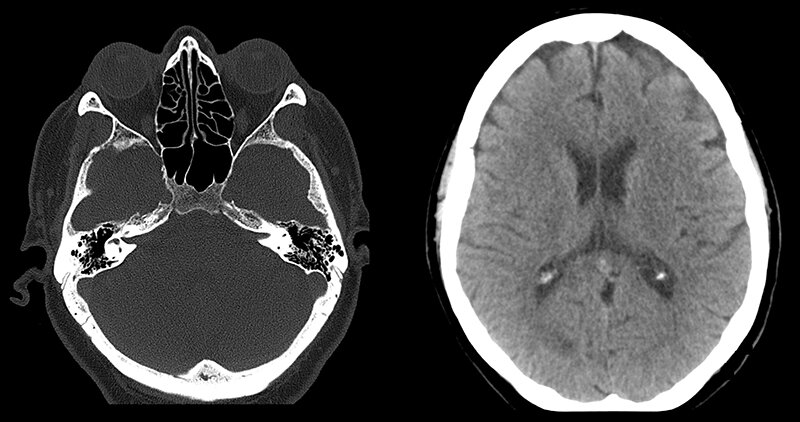

КТ головы. Источник: hospitalfts.ru